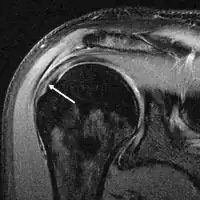

МРТ

Магнитно-резонансная томография (МРТ) и ультразвук[39] сравнимы по эффективности и полезны в диагностике, хотя оба имеют ложноположительный уровень 15-20 %.[40] МРТ может надёжно обнаружить большинство разрывов на всю толщину, хотя очень маленькие точечные разрывы можно не заметить. В таких ситуациях МРТ в сочетании с инъекцией контрастного вещества, МР-артрограмма может помочь подтвердить диагноз. Следует понимать, что обычная МРТ не может полностью исключить небольшой разрыв (ложноотрицательный результат), в то время как разрывы частичной толщины не могут быть обнаружены с такой надежностью.[41] Хотя МРТ чувствительна к выявлению дегенерации сухожилия (тендинопатии), она не может надежно отличить дегенеративное сухожилие от частично разорванного сухожилия. Опять же, магнитно-резонансная артрография может улучшить дифференциацию.[41] Её общая чувствительность — 91 % (то есть 9 % ложноотрицательных результатов), таким образом магнитно-резонансная артрография является надёжной при обнаружении разрывов частичной толщины вращающей манжеты манжеты.[41] Однако его обычное использование не рекомендуется, поскольку оно связано с введением в сустав иглы с потенциальным риском заражения. Следовательно, тест предназначен для случаев, когда диагноз остается неясным.